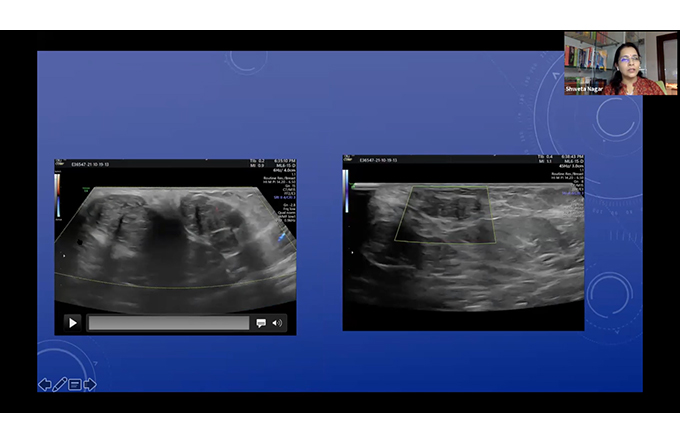

Color doppler in Obstetrics - what each vessel tells us?

KREST Doppler Course

KREST Kochi

60 Min